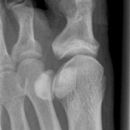

Großzehe seitlich 2. Ebene

Lagerung

Fuß mit der medialen Seite aufliegend

die anderen Zehen mit Band zurückziehen

Senkrecht auf Objektmitte

Seitliche Darstellung der Großzehe einschließlich Großzehengrundgelenk.